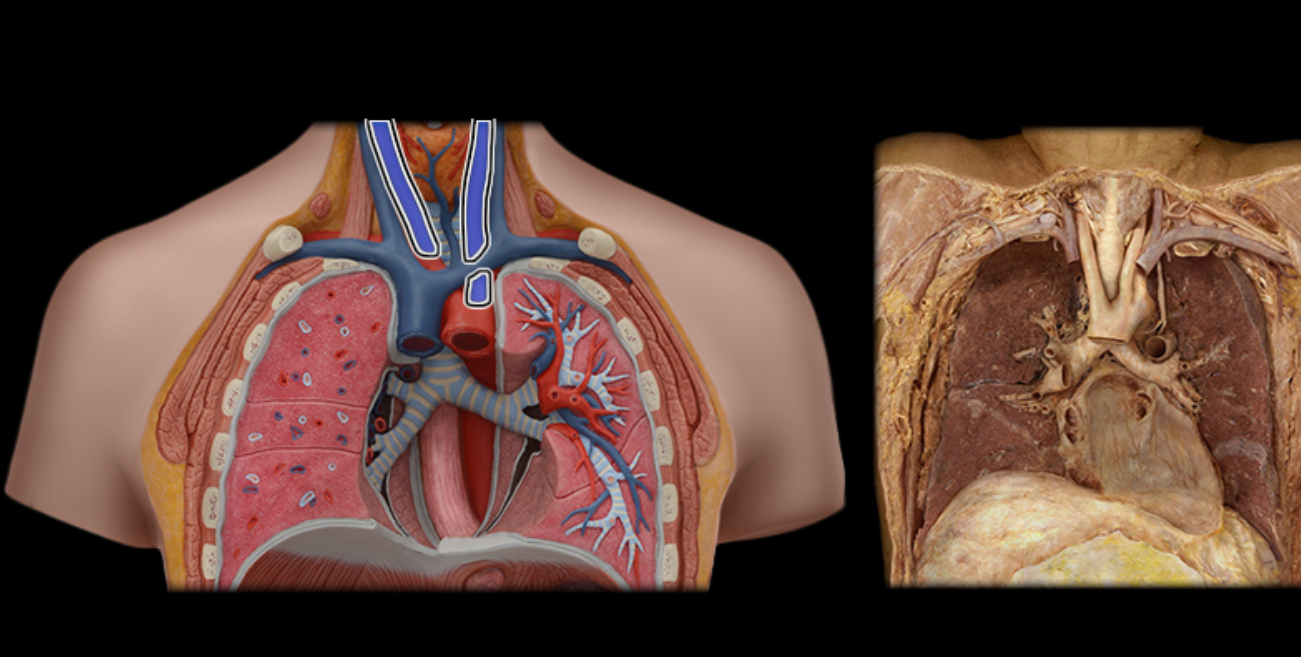

Arch of aorta

Brachiocephalic trunk

Inferior vena cava

Pulmonary trunk

Superior vena cava

Ascending aorta

Pulmonary trunk

Brachiocephalic v.

Pulmonary a.

Pulmonary vv.